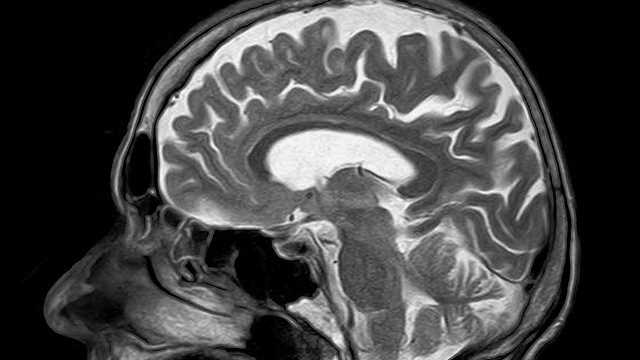

(MRI 뇌사진)

MRI 검사는 뇌의 기관을 자세히 보고자 하는 검사입니다. 혈관보다는 뇌가 잘 보이는 검사죠. 아마 위의 사진을 보시면 더 이해가 빠르실 겁니다. 혈관 보다는 뇌의 기관이 더 잘보이죠? 그렇기 때문에 치매 검사, 뇌종양 검사, 등의 이상이 있는지를 빠르게 보고 자세하게 볼 수 있는 검사죠.